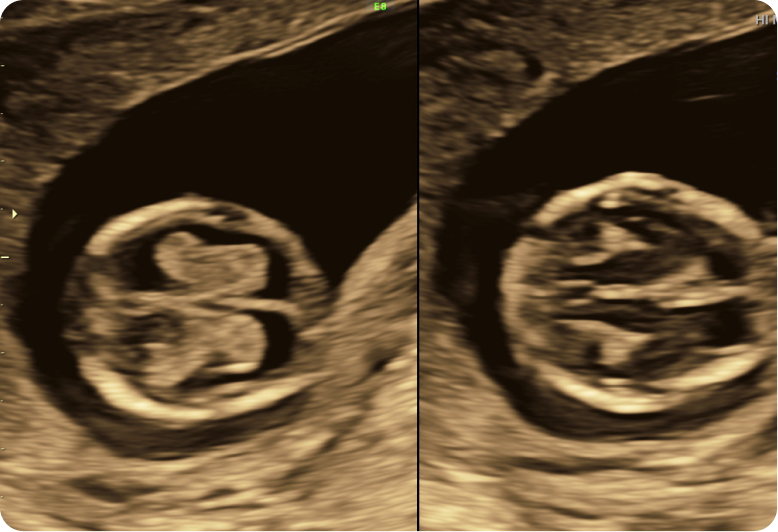

The NT scan is a non-invasive ultrasound test used to assess the risk of chromosomal abnormalities like Down syndrome. It measures the thickness of a fluid-filled space at the back of the baby’s neck (nuchal fold) and evaluates the nasal bone.

This scan also helps in the early detection of certain structural abnormalities, providing valuable insights into your baby’s health.

NT scan specifically measures the nuchal translucency and assesses the nasal bone and thus helps in detecting the risk of the baby for chromosomal abnormalities.